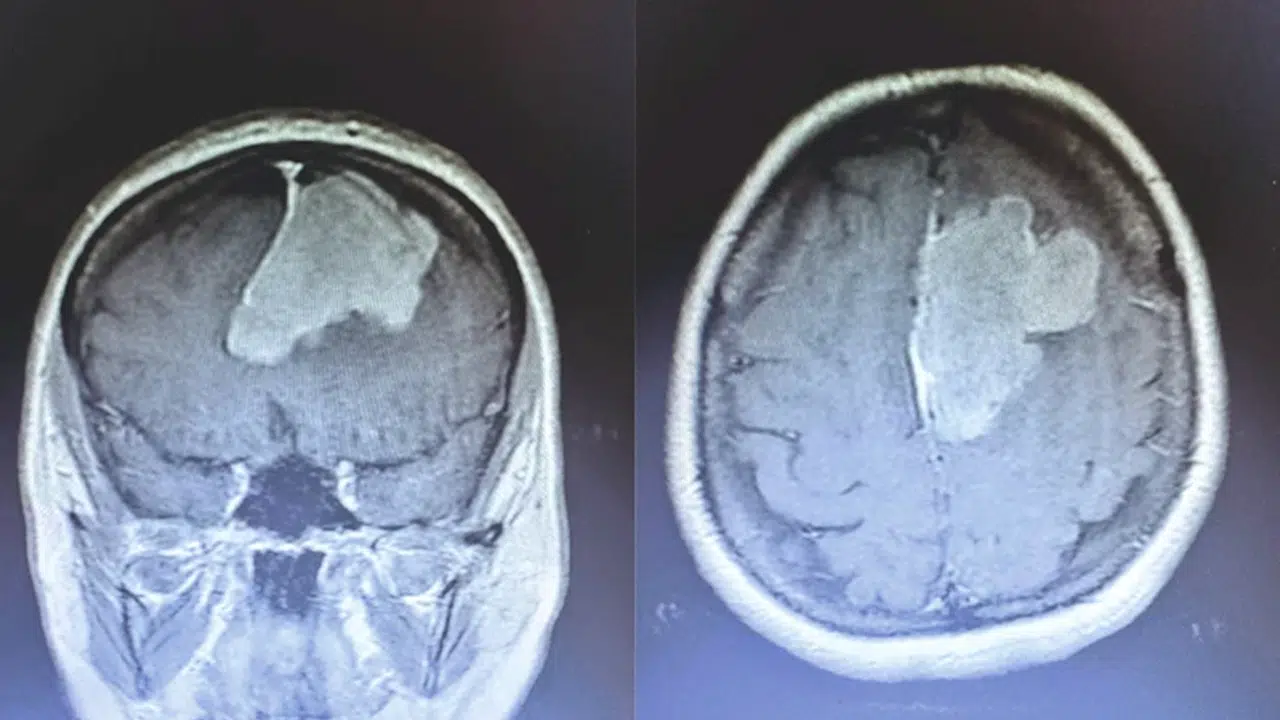

Erbaa'da beyin tümörü ameliyatı yapıldı

TOKAT (AA) - Tokat'ın Erbaa ilçesinde beyin tümör ameliyatı gerçekleştirildi.

İl Sağlık Müdürlüğünden yapılan yazılı açıklamaya göre, Ayfer Polat, rahatsızlığı sebebiyle Erbaa Devlet Hastanesi Beyin ve Sinir Hastalığı servisine başvurdu.

Yapılan tetkiklerde Polat'ın ameliyat olması gerektiği belirlendi.

Polat'ın nöronavigasyon eşliğinde mikroskopik yaklaşımla beyin tümörü ameliyatı, Erbaa Devlet Hastanesinde yapıldı.

Hastanede ikinci kez yapılan ameliyat, beyin ve sinir cerrahisi uzmanı operatör Dr. Ali Kalpan tarafından gerçekleştirildi.